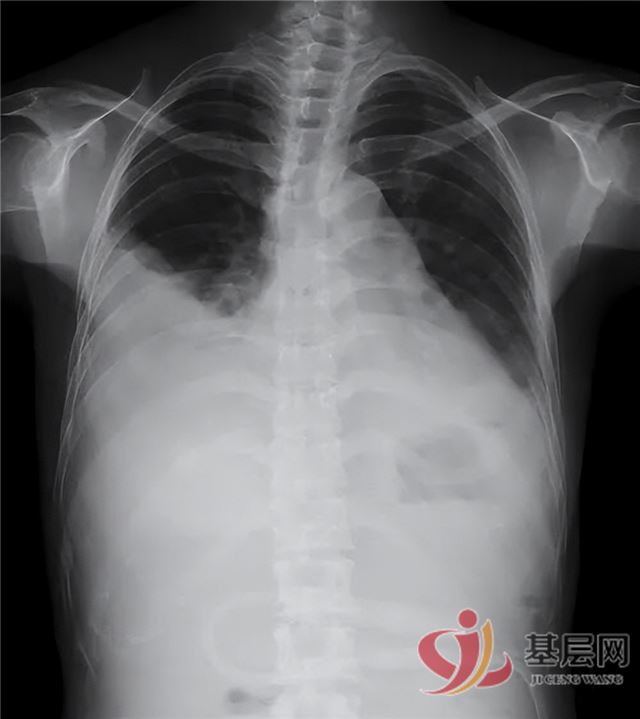

随着靶向治疗持续进行,联合中药扶正调理,姜奶奶的胸腔积液逐渐吸收,症状显著缓解:胸闷气促、咳嗽咳痰、恶心反酸等均明显减轻,食欲增加,体力恢复,活动耐量提升。治疗一周后,胸腔引流管顺利拔除。出院一月随访,复查显示右侧胸水完全吸收,左侧仅存少量包裹性积液,血常规、肝肾功能正常,患者整体状况良好,生活质量显著提高。